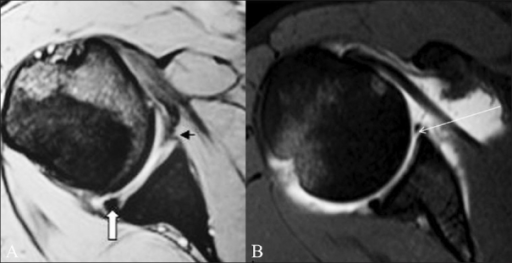

Clinical image for Anterior Shoulder Instability

What imaging would you order? How do you quantify bone loss and what are the critical thresholds?